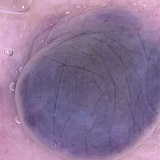

Внешне голубой невус Ядассона–Тиче представляет собой небольшого размера (до 8–10 мм в диаметре) плоскую или слегка приподнятую над кожей родинку. Поверхность такой родинки гладкая, без явной бугристости. Цвет может варьировать от голубого до тёмно-синего, причем окраска неравномерная из-за достаточно глубокого залегания образующих опухоль меланоцитов. В некоторых случаях размер невуса больше стандартного — до 3–3,5 см. Контур невуса не всегда четкий. Форма бывает круглая, вытянутая или веретенообразная. Ни равномерность окраса, ни форма родинки не является указателем на необходимость удаления или отсутствие такой потребности.

Клеточная форма отличается от неклеточной размерами — родинки такого типа в диаметре не менее полутора сантиметров. Из-за неоднородной по насыщенности окраски и часто встречающейся бугристой «рыхлой» поверхности его можно принять за меланому, формы которой могут иметь схожий набор признаков. Наиболее часто встречающиеся места локализации такого невуса — поясница и ягодицы, реже — кисти и стопы.

Ставить диагноз должен только врач, самодиагностика при данном виде опухоли недопустима ввиду ее меланомоопасности. При диагностике голубого невуса прибегают к дерматоскопии. При помощи дерматоскопа врач может оценить границы невуса, однородность, глубину залегания меланоцитов. Последнее особенно важно, поскольку при нормальном течении этот тип родинки не обязателен к удалению — с таким невусом вполне можно жить, если он не мешает и не изменяется.

Голубой невус: дифференциальная диагностика